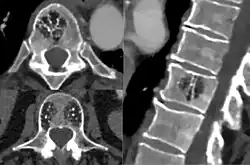

Диагностика

Для диагностики младенческих гемангиом достаточно пройти консультацию у специалиста, занимающегося лечением данной патологии и сделать УЗИ. Выполнение КТ, МРТ, ангиографии выполняется в редких случаях, когда затруднительно установить точный диагноз или при подозрении, например, на наличие образований в просвете гортани.